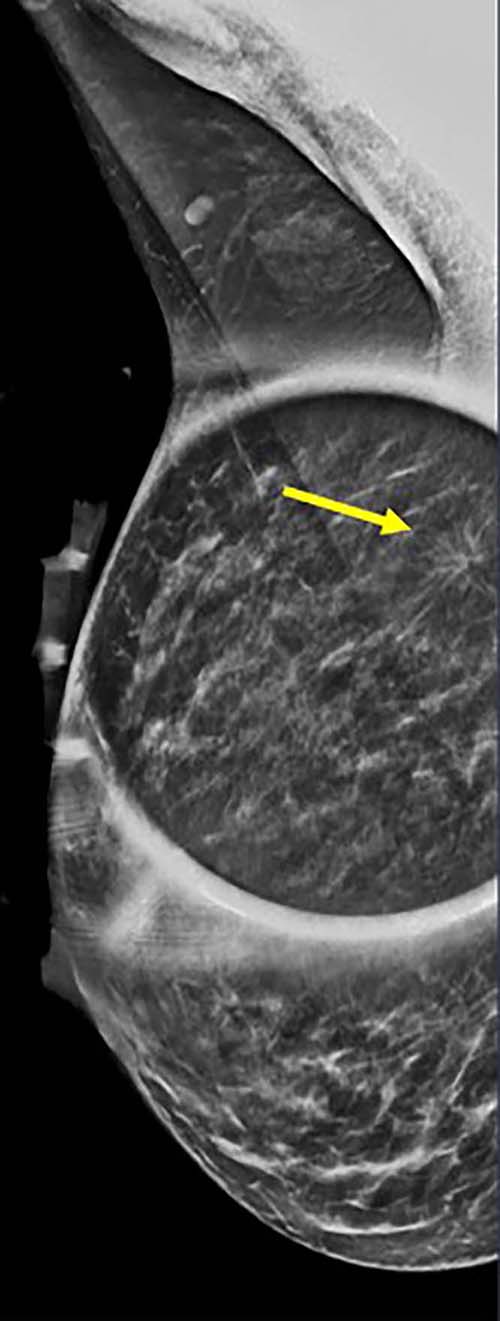

Figure 3. Spot on right mediolateral oblique (side angle) view. Area of distortion persists on additional mammographic views, and a mass is identified on subsequent breast ultrasound. Ultrasound guided biopsy was performed and revealed nuclear grade 1 invasive ductal carcinoma.